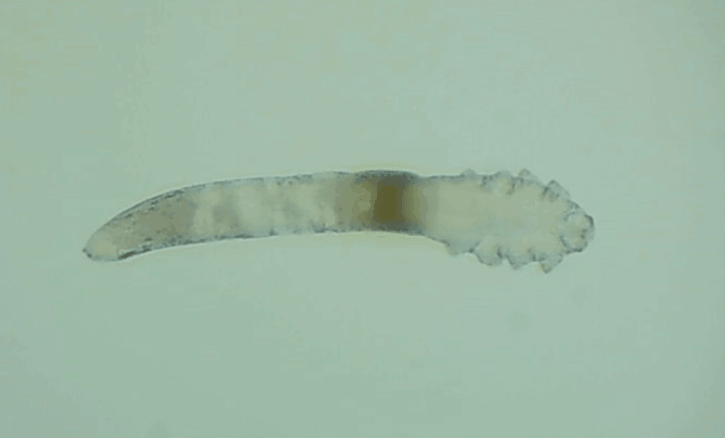

是的, 眼睛也會有蟲子,那就是蠕形螨。眼睛發(fā)紅、干癢、疲勞、睫毛脫落,這些都是因為它。

其實蠕形螨主要活動在毛囊和皮脂腺中,以皮膚碎屑和腺體分泌物作為食物來源,而睫毛根部的瞼板腺是排泄油脂的重要部位,因此眼睫毛和瞼板腺也是螨蟲的主要活動場所。

一般來說,15天內(nèi),一只蠕形螨會在你眼睛里產(chǎn)下50只蟲卵。如果不及時除螨,它們會迅速繁殖,從而導(dǎo)致睫毛脫落、亂生、眼睛紅癢,甚至引發(fā)眼部炎癥。如果影響到角膜,就會造成視力下降甚至失明。